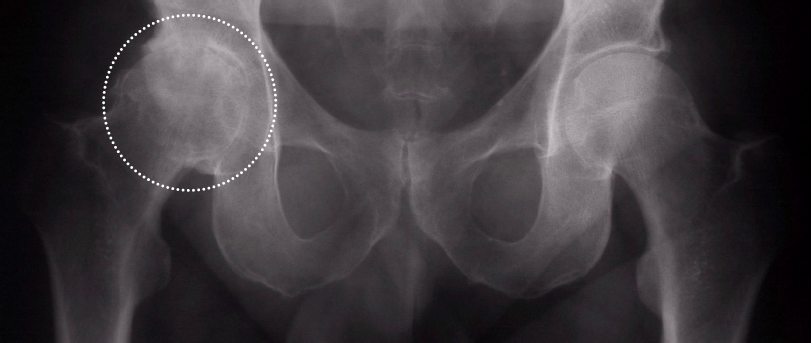

Qu’est-il vraiment important de différencier à la radiographie?

Il est important, sur la base d’une radiographie simple, de faire la différence entre une atteinte mécanique et une atteinte inflammatoire.

L’arthrose représente une atteinte mécanique de l’articulation avec une usure asymétrique du cartilage, en fonction des forces mécaniques exercées au niveau de l’articulation malade. De façon classique, seulement la zone de charge sera affectée par le phénomène arthrosique.

Dans une atteinte inflammatoire, il s’agit d’une atteinte concentrique diffuse qui engendrera des pincements articulaires diffus sur toute la surface articulaire malade.

Ex, sur la photo de gauche, c’est de l’arthrose, à droite, c’est inflammatoire.